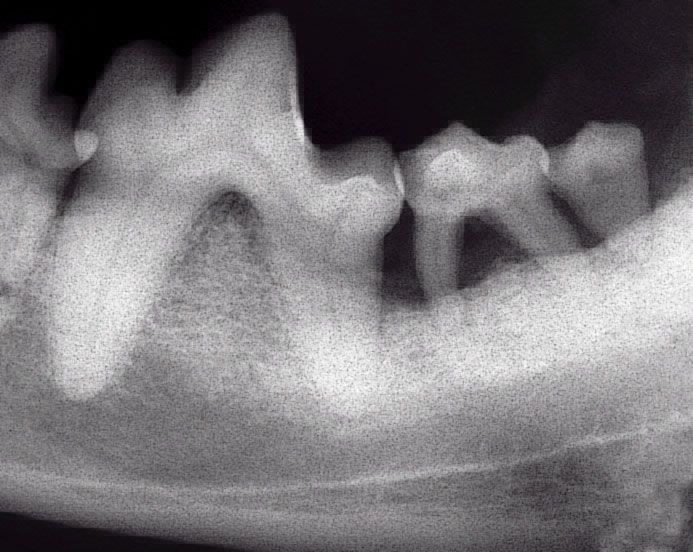

Radiograph showing up to 50% bone loss